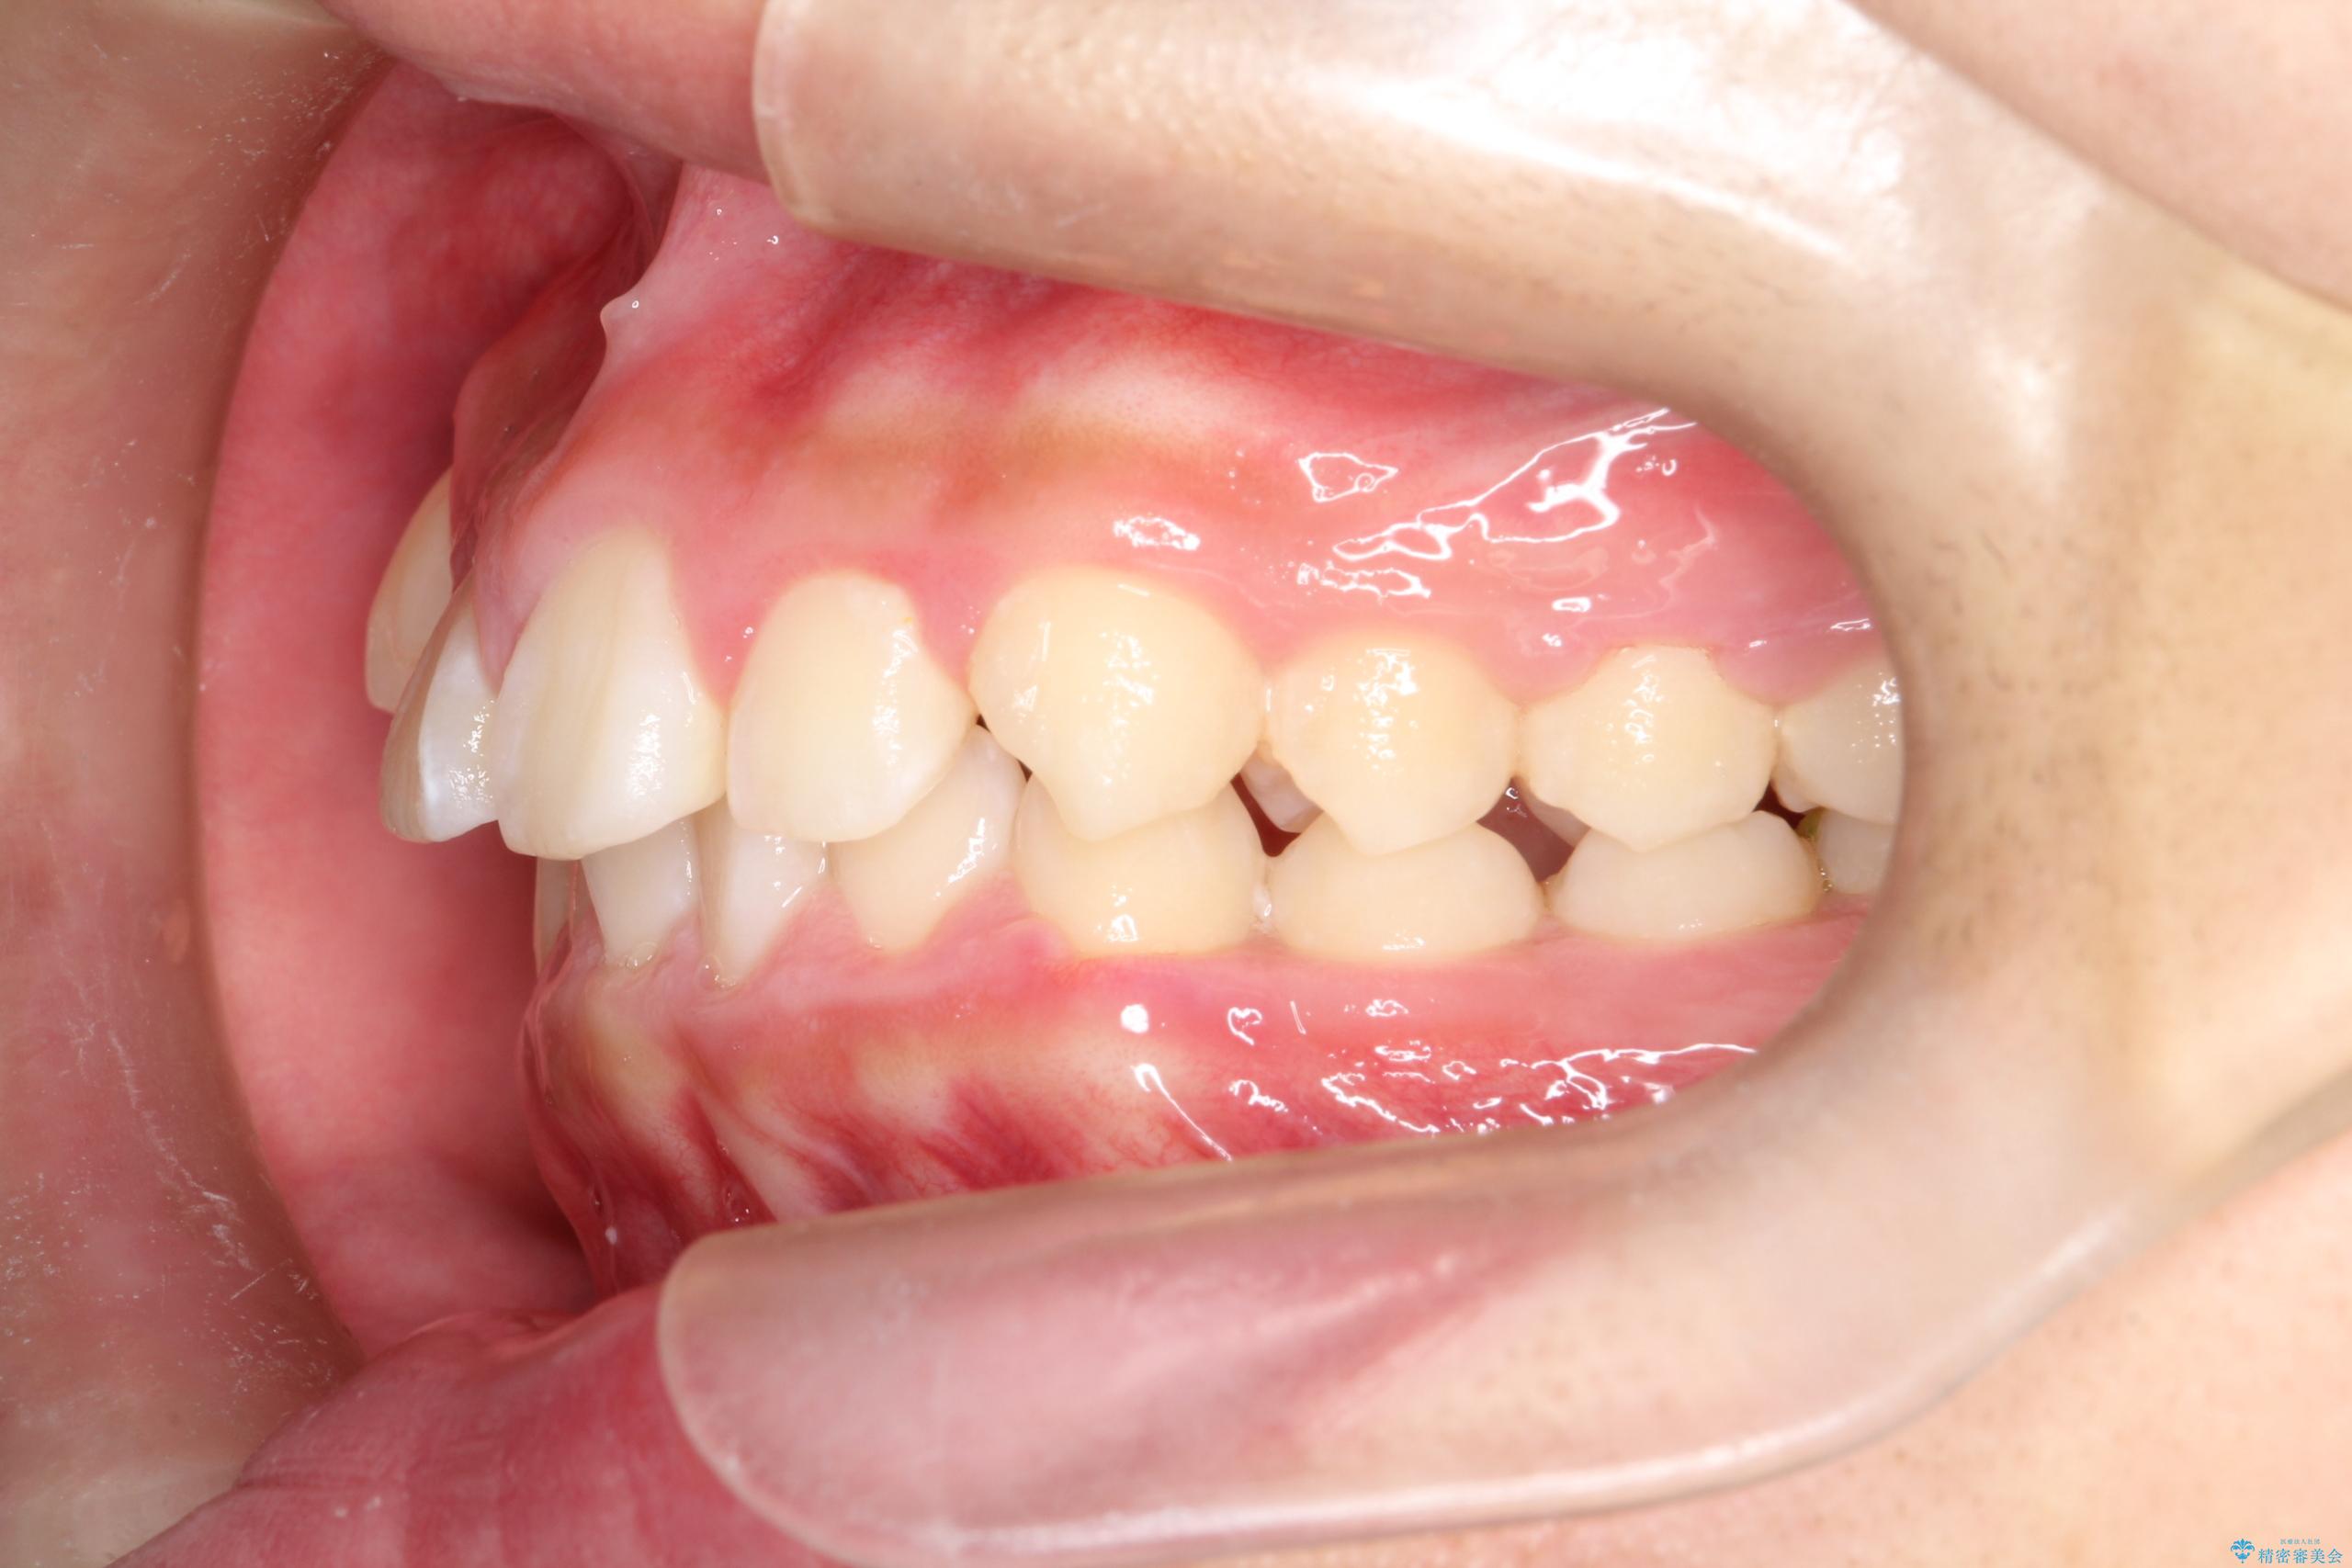

- 八重歯と咬み合わせを治したいを主訴にご来院された患者様です。

八重歯などの歯列のデコボコが綺麗に改善され、患者様にも大変喜んでいただけました。また、咬み合わせが深い「ディープバイト」も併せて改善し、見た目だけでなく機能面でもバランスの取れた咬合を獲得しています。